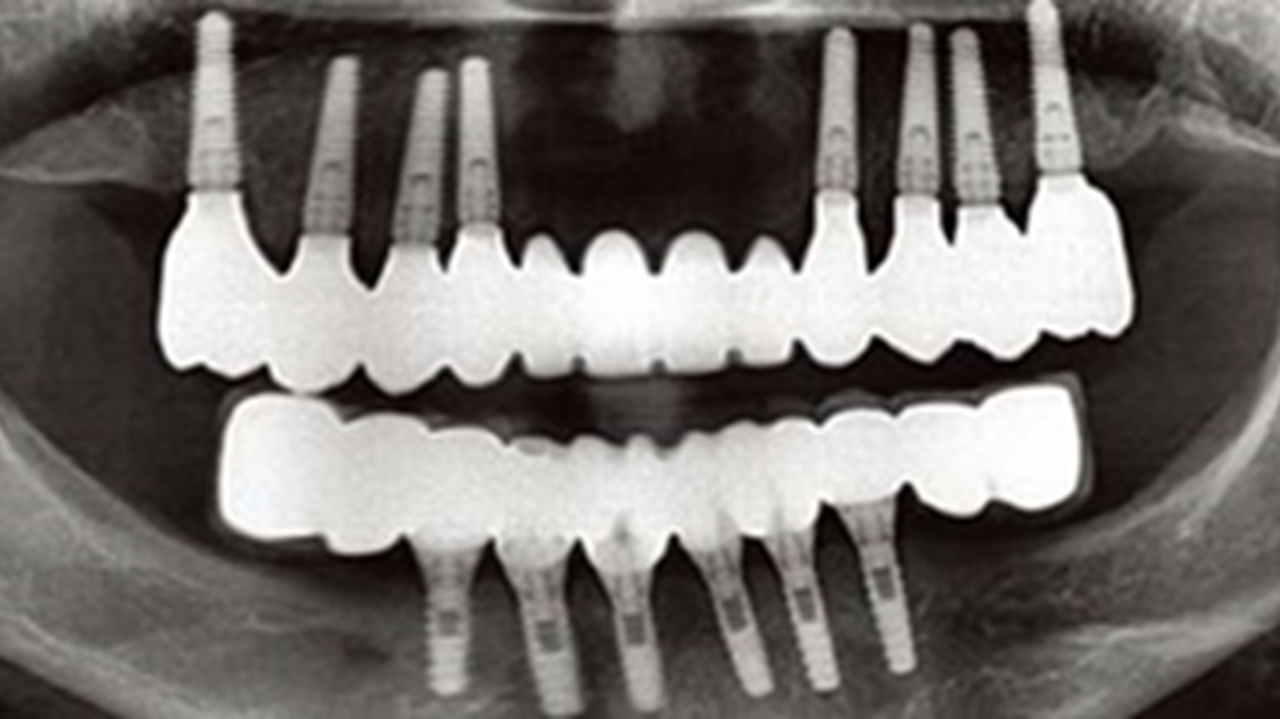

Clinical case: Advantage of fuse abutment with AnyRidge implant for immediate loading in

upper fully edentulous case

“AnyRidge shows excellent initial stability

& stable results after immediate loading in

upper fully edentulous case. ”